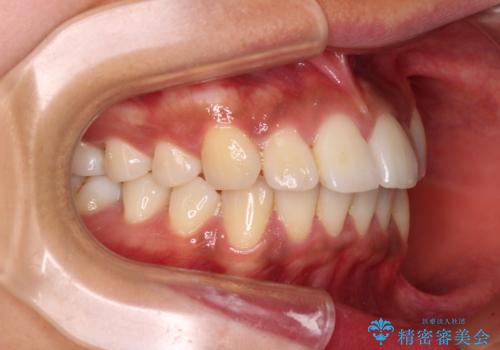

- 全体的な歯列の叢生を気にして来院された患者様です。

奥歯の咬み合わせを見ると、片方は上顎が下顎に対して相対的に前方にある状態でした。

咬み合わせを改善するためには、上顎臼歯を後方に移動させた咬み合わせにする必要があります。

インビザライン単体で改善することも可能ですが、ディープバイトのためインビザライン単体で達成する可能性が低いと考えられたため、カリエール・ディスタライザーという補助装置を併用して、より確実性を上げることとしました。

奥歯の咬み合わせ改善後に、インビザラインにて歯列を整えることとしました。

カリエールディスタライザーを併用したことで、確実かつ短期間で治療を終えることができました。